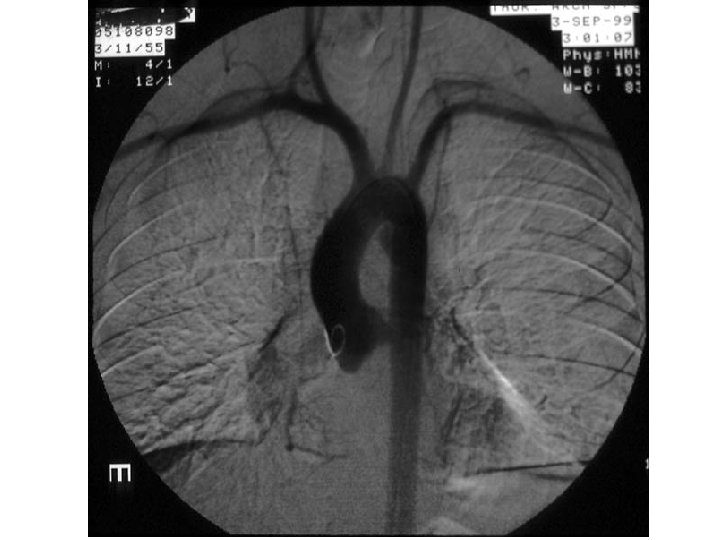

Aneurysms

Aneurysma ACA